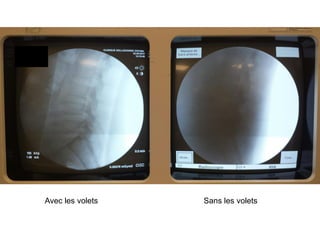

Diaphragme, volets,

collimateurs… synonymes

de diminution de la dose

et amélioration de la

qualité de l’image

(contraste)

« kaléidoscope » « barres »

Principes : 1°) les paramètres d’acquisition automatiques de l’image ne

tiennent compte que de la zone à observer (élimine par exemple l’air

beaucoup moins dense)

2°) réduit l’arrivée sur le capteur des rayons difractés par le

patient qui n’apportent pas une information géométriquement correcte

Avec les volets Sans les volets